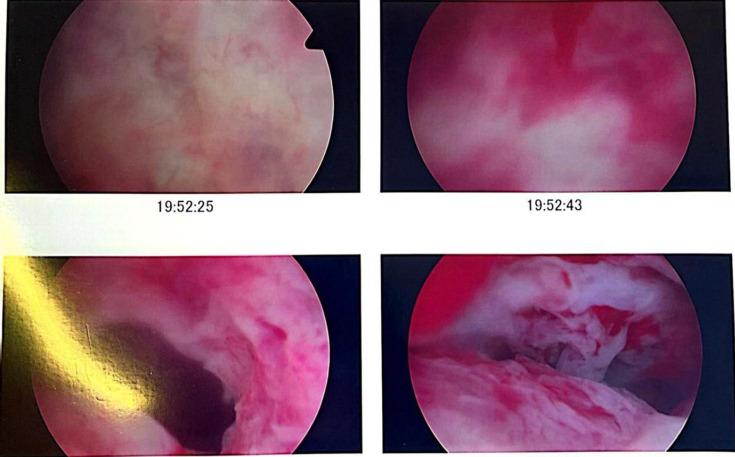

Histiocytic or xanthogranulomatous endometritis (XGE) is an extremely rare benign histopathological entity with only a few cases reported in literature to date. It is characterised by the replacement of endometrial tissue with sheets of foamy histiocytes, giant cells, lymphocytes and plasma cells; calcification and necrosis. It involves chronic inflammation and may be associated with endometrial hyperplasia, endometrial carcinoma and atrophy, causing cervical stenosis and recurrent pyometra, especially in postmenopausal women. We report a case of senile recurrent pyometra masquerading as pyelonephritis clinically and endometrial malignancy radiologically, confirmed later on histology as XGE. Due to deceptive manifestation and rarity of this clinical condition, it is very important for a gynaecologist, radiologist and histopathologist to have a clear understanding of this entity.

组织细胞性或黄色肉芽肿性子宫内膜炎(XGE)是一种极其罕见的良性组织病理学实体,迄今为止文献中仅报道了少数病例。其特征是子宫内膜组织被成片的泡沫状组织细胞、巨细胞、淋巴细胞和浆细胞取代;伴有钙化和坏死。它涉及慢性炎症,可能与子宫内膜增生、子宫内膜癌和萎缩相关,导致宫颈狭窄和复发性脓性子宫积脓,尤其是在绝经后女性中。我们报告一例老年复发性脓性子宫积脓病例,临床上伪装为肾盂肾炎,放射学上疑似子宫内膜恶性肿瘤,后来经组织学确诊为XGE。由于这种临床情况的表现具有欺骗性且罕见,妇科医生、放射科医生和组织病理学家清楚了解这一实体非常重要。